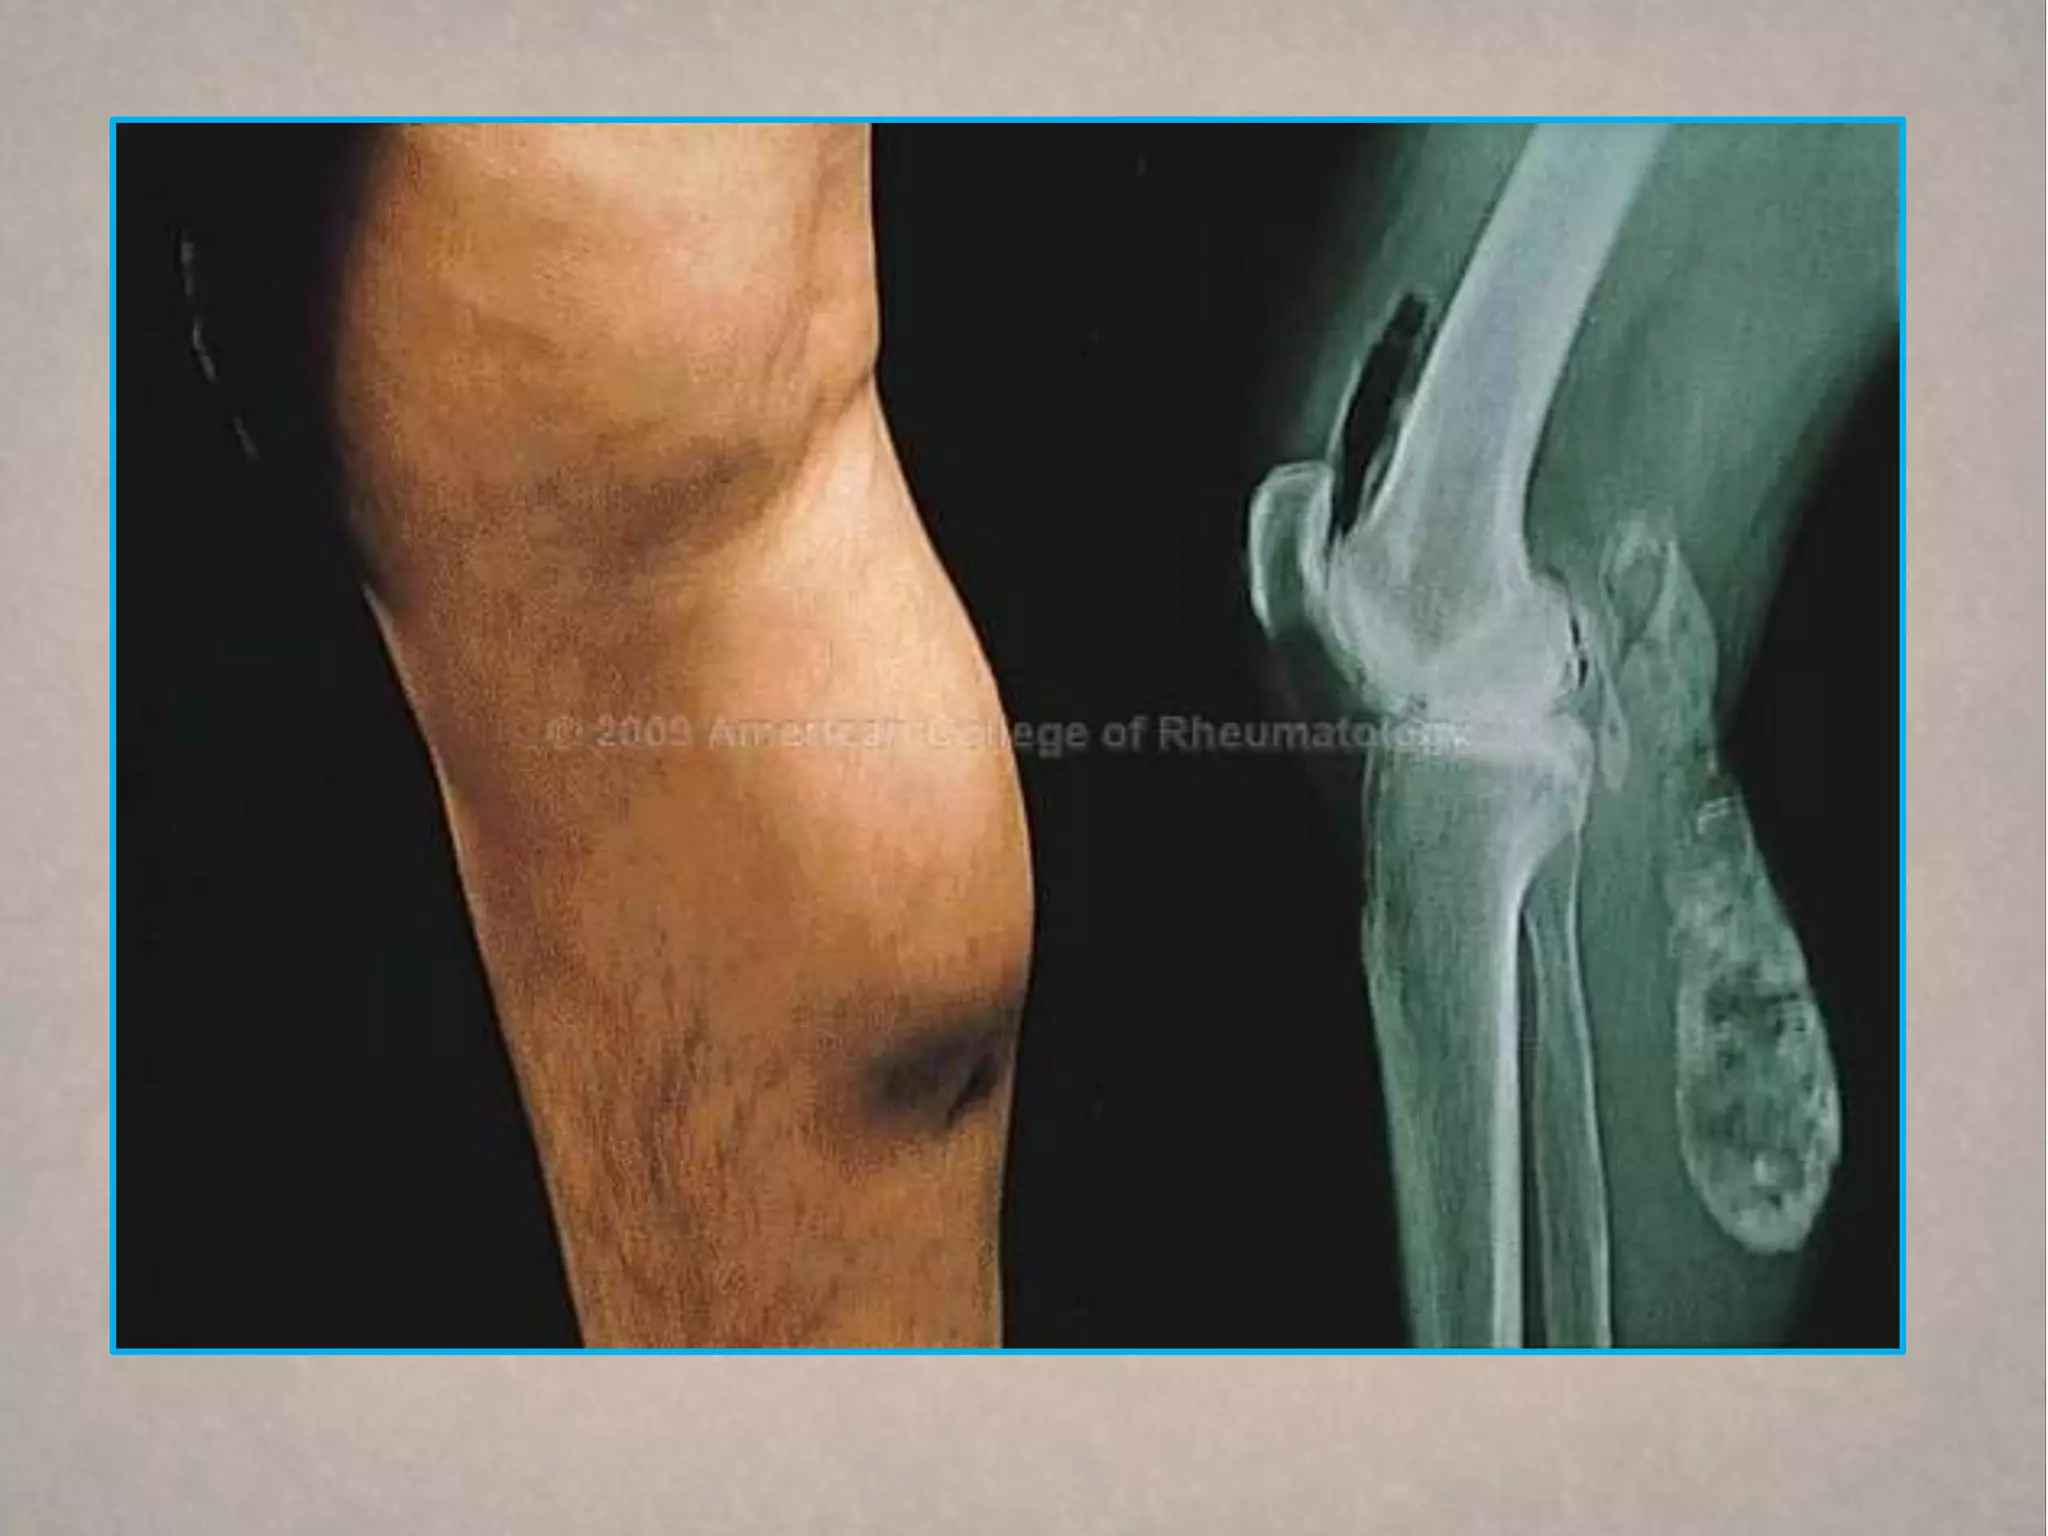

Venous insufficiency

Venous insufficiency is characterized by chronic pitting edema,

often associated with brown hemosiderin skin deposits on the

lower legs. The skin changes can progress to dermatitis and

ulceration, which usually occur over the medial maleoli. Other

common findings include varicose veins and obesity. Most patients

are asymptomatic but a sensation of aching or heaviness can

occur. The diagnosis is usually made clinically but can be

confirmed with a Doppler study. Although chronic venous

insufficiency is thought to result from previous deep vein

thrombosis, only one third of patients will give that history

compression stockings

Venous insufficiency Venousinsufficiency is characterized by chronic pitting edema, often associated with brown hemosiderin skin deposits on the lower legs. The skin changes can progress to dermatitis and ulceration, which usually occur over the medial maleoli. Other common findings include varicose veins and obesity. Most patients are asymptomatic but a sensation of aching or heaviness can occur. The diagnosis is usually made clinically but can be confirmed with a Doppler study. Although chronic venous insufficiency is thought to result from previous deep vein thrombosis, only one third of patients will give that history compression stockings